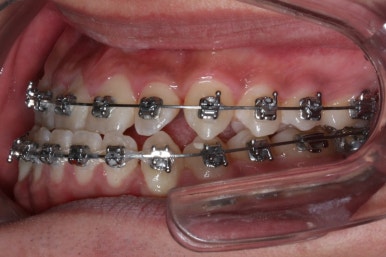

점점 수술전 교정이 진행되는 모습입니다.

각각의 위턱과 아래턱뼈 제위치에 맞게 윗니는 뒤로, 아랫니는 앞으로 내어주게 됩니다. 수술직전까지는 어떻게 보면 교합은 점점 나빠진다고 볼 수 있씁니다.

이 과정에서 힘들어 하시는 분들이 많으신데요. 점점 교합이 서로 멀어질수록 수술은 예쁘게 잘 된답니다.